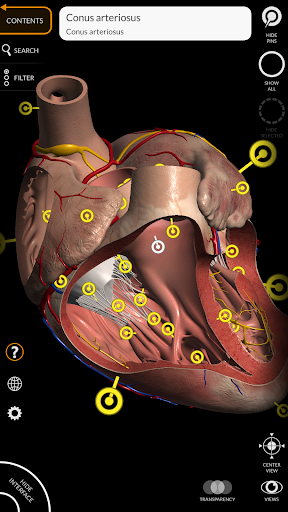

"Anatomía - Atlas 3D" permite estudiar la anatomía humana de forma fácil e interactiva.

A través de una interfaz sencilla e intuitiva es posible observar cada estructura anatómica desde cualquier ángulo.

Los modelos anatómicos 3D son especialmente detallados y con texturas de hasta una resolución de 4k.

• Sistema cardiovascular • Sistema

nervioso • Sistema respiratorio • Sistema digestivo • Sistema urogenital (masculino y femenino) • Sistema endocrino • Sistema linfático • Sistema ocular y auditivo CARACTERÍSTICAS • Interfaz sencilla e intuitiva • Rotar y hacer zoom en cada modelo en el espacio 3D • Opción para ocultar o aislar uno o varios modelos seleccionados • Filtro para ocultar o mostrar cada sistema • Función de búsqueda para encontrar fácilmente cada parte anatómica • Función de marcador para guardar vistas personalizadas • Rotación inteligente que mueve el centro de rotación automáticamente • Función de transparencia • Visualización de músculos a través de niveles de capas desde las superficiales hasta las más profundas • Al seleccionar un modelo o un pin, aparece el término anatómico relacionado • Descripción de los músculos: origen, inserción, inervación y acción • Mostrar/ocultar interfaz de usuario (muy útil con pantallas pequeñas) MULTILINGÜE • Los términos anatómicos y la interfaz de usuario están disponibles en 11 idiomas: latín, inglés, francés, alemán, italiano, portugués, turco, ruso, español, Chino, japonés y coreano • Los términos anatómicos se pueden mostrar en dos idiomas simultáneamente REQUISITOS DEL SISTEMA • Android 8.0 o posterior, dispositivos con al menos 3 GB de RAM Reversi

• Sistema cardiovascular